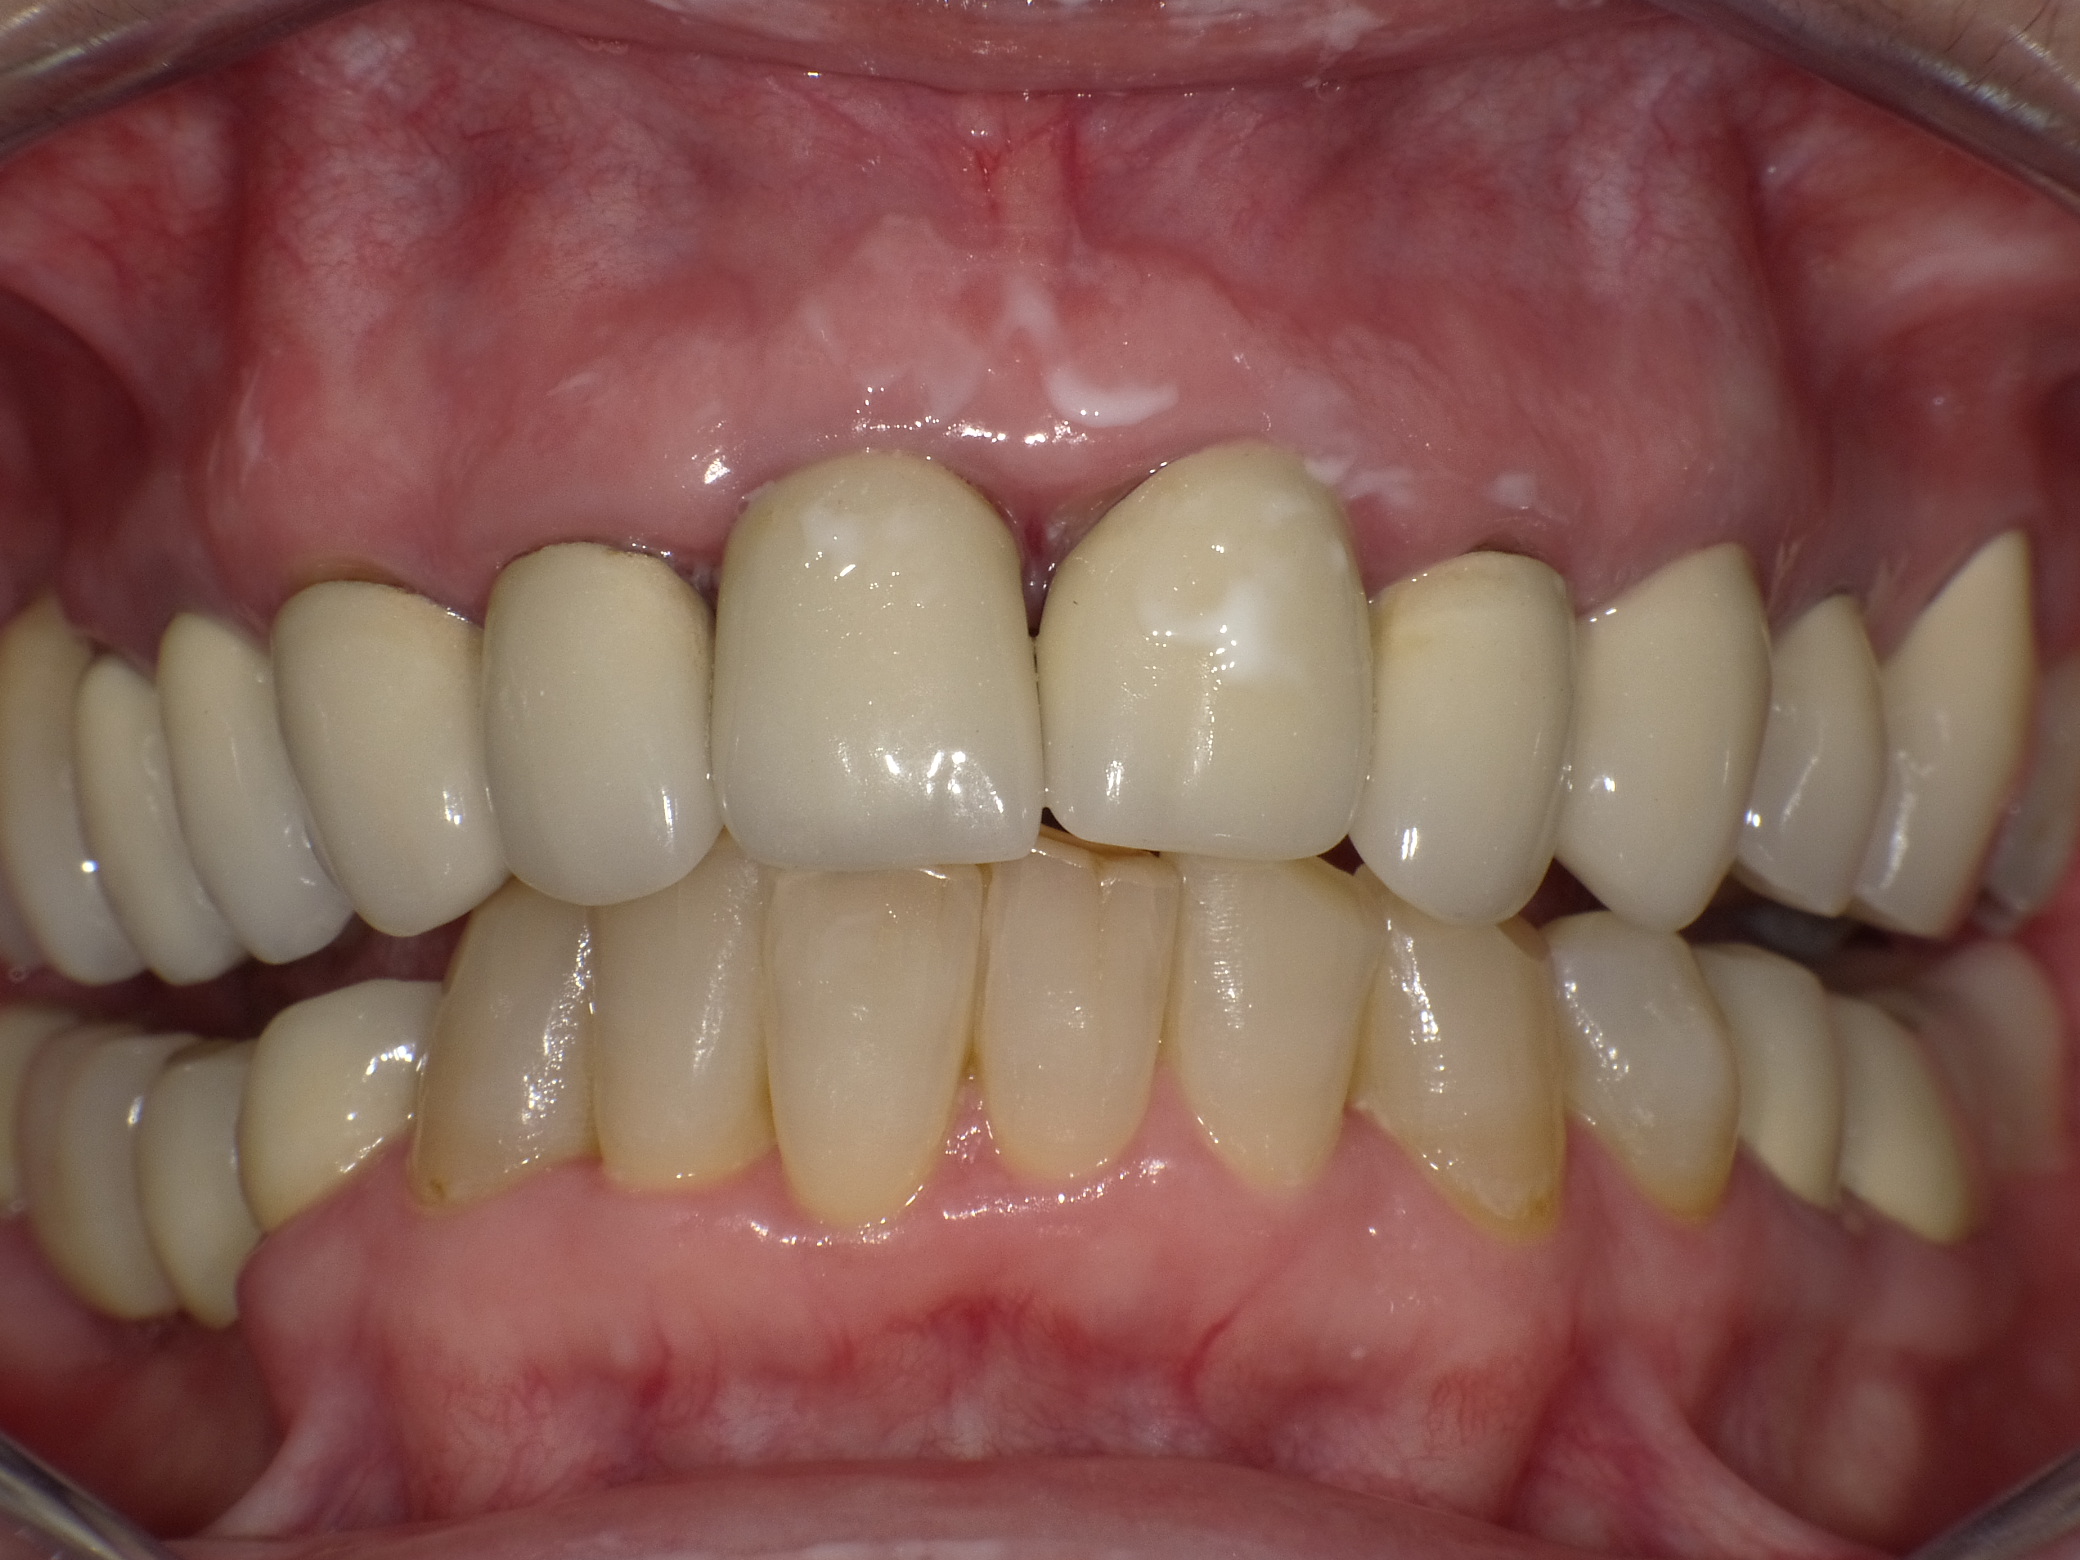

Diverse Vorbehandlungen mit für die Patientin absolut inakzeptablem Ergebnis

Vorher: Diverse Vorbehandlungen mit für die Patientin absolut inakzeptablem Ergebnis

Komplette Veränderung mit vollkeramischen Kronen und Veneers in nur 2 Langzeitterminen; auch hier nachher ganz anderes Auftreten der Patientin, die ihre Zähne jetzt gerne zeigt und wieder gerne lacht

Nachher: Komplette Veränderung mit vollkeramischen Kronen und Veneers in nur 2 Langzeitterminen; auch hier nachher ganz anderes Auftreten der Patientin, die ihre Zähne jetzt gerne zeigt und wieder gerne lacht